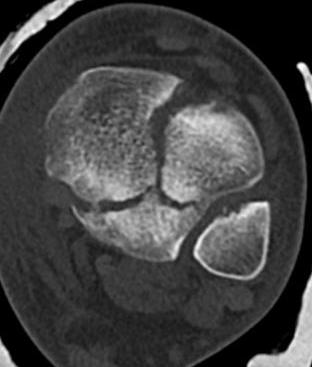

CT

Coronal images: Salter-Harris type III

Sagittal images: Salter-Harris type II

Axial images: 3 point star